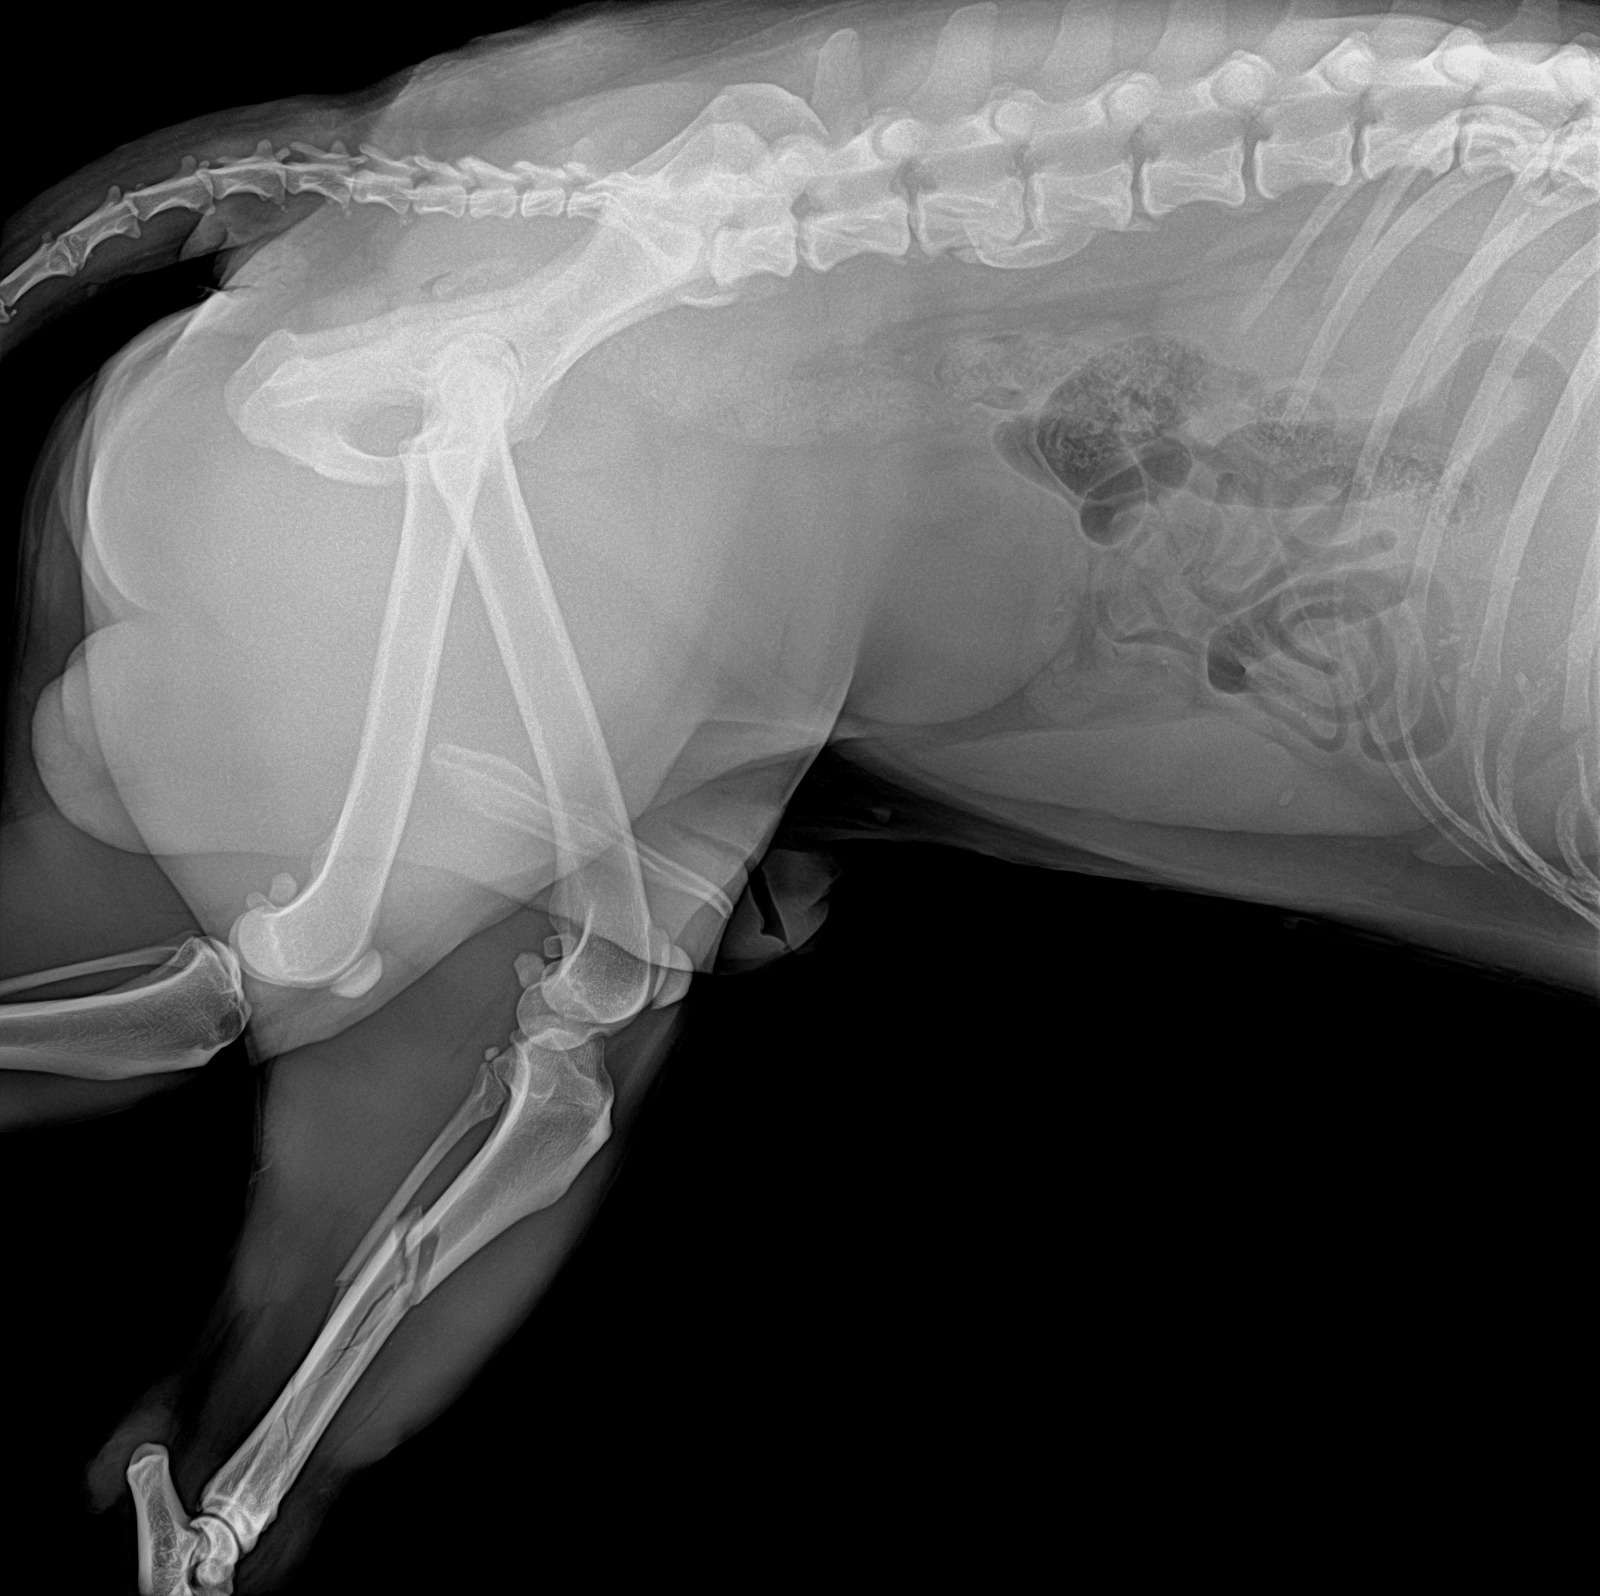

Hello Everyone, this sweet boy is Ace (his rescue name) he was found on December 25 injured and with a broken leg, he entered a local store to try to seek shelter after he was likely hit by a car and got into a fight with another dog, he has multiple bite wounds all over his body and his tibia is shattered.

Once we got the results of the x-rays and his check up we realized the we likely would not be able to cover the bill on our own, but we don't want to leave Ace to his own luck so we've decided to start this gofundme to try and get the money for his surgery and subsequent recovery as he will need a lot of care and love before he is ready to look for a forever home that will love and care for him for the rest of his life.